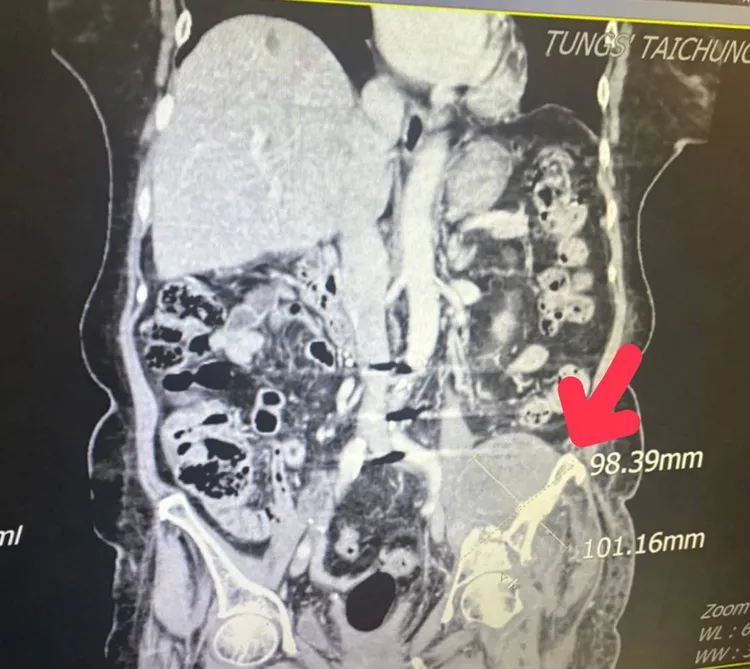

銳視刀治療後腫瘤已經縮小至9.8公分x10.1公分左右。童綜合醫院提供